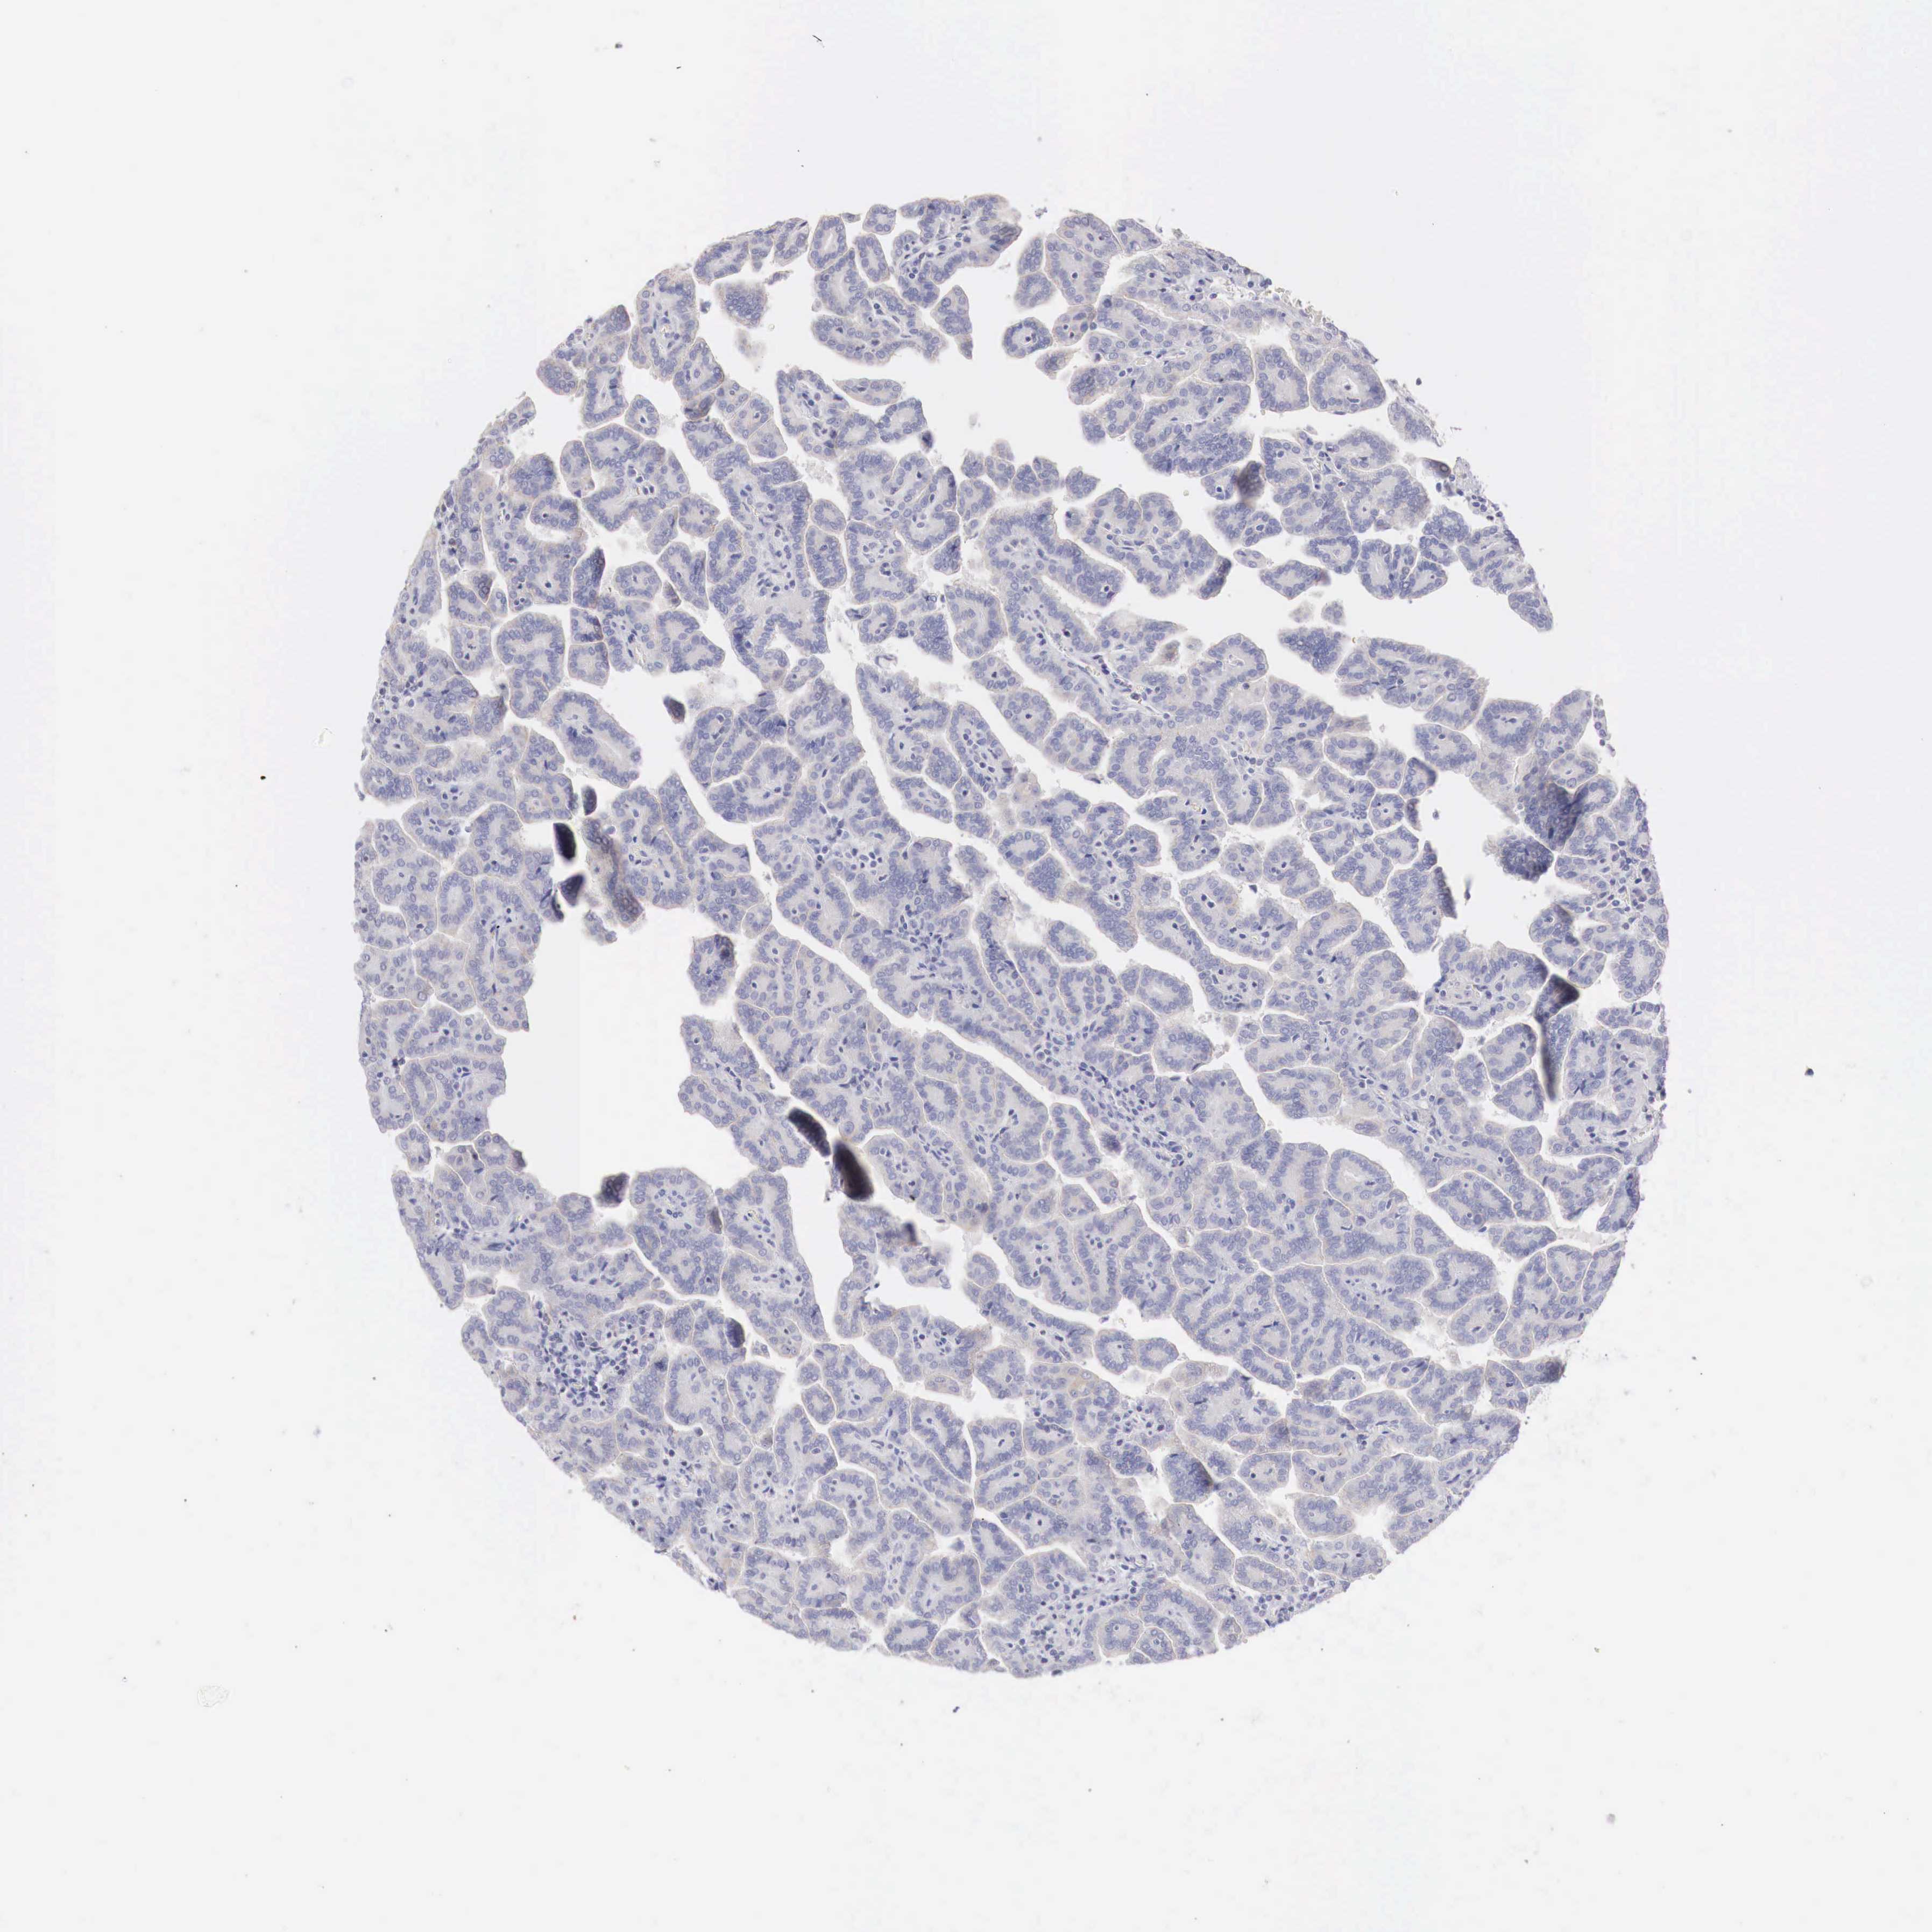

KIDNEY RENAL CLEAR CELL CARCINOMA (VALIDATION) - Interactive survival scatter ploti

The Survival Scatter plot shows the clinical status (i.e. dead or alive) for all individuals in the patient cohort, based on the same data that underlies the corresponding Kaplan-Meier plots. Patients that are alive at last time for follow-up are shown in blue and patients who have died during the study are shown in red.

The x-axis shows the expression levels (FPKM) of the investigated gene in the tumor tissue at the time of diagnosis. The y-axis shows the follow-up time after diagnosis (years). Both axes are complimented with kernel density curves demonstrating the data density over the axes. The top density plot shows the expression levels (FPKM) distribution among dead (red) and alive patients (blue). The right density plot shows the data density of the survived years of dead patients with high and low expression levels respectively, stratified using the cutoff indicated by the vertical dashed line through the Survival Scatter plot. This cutoff is automatically defined based on the FPKM cutoff that minimizes the p-score. The cutoff can be changed by dragging the vertical line or by entering a cutoff value in the square labeled "Current cut-off".

Under the Survival Scatter plot the p-score landscape (black curve; left axis) is shown together with dead median separation (red curve; right axis). Dead median separation is the difference in median mRNA expression between patients who have died with high and low expression, respectively. It is calculated as follows: median FPKM expression of dead patients with high expression - median FPKM expression of dead patients with low expression. This is intended to aid the user in visually exploring custom cutoffs and the associated p-scores and dead median separation.

Individual patient data is displayed and can be filtered by clicking on one or more of the category buttons on the top of the page. Categories describing expression level and patient information include: high, low, alive, dead, female, male and tumor stages. The scale of the x-axis can be toggled between linear and log-scale by clicking on the "x log" button. Mouse-over function shows TCGA ID, patient information and mRNA expression (FPKM) for each patient.

& Survival analysisi

Kaplan-Meier plots summarize results from analysis of correlation between mRNA expression level and patient survival. Patients were divided based on level of expression into one of the two groups "low" (under cut off) or "high" (over cut off). X-axis shows time for survival (years) and y-axis shows the probability of survival, where 1.0 corresponds to 100 percent.

TRIM13 is validated prognostic, high expression is favorable in Kidney Renal Clear Cell Carcinoma (validation)

: 25.87

Average pTPM 25.6

Number of samples 100